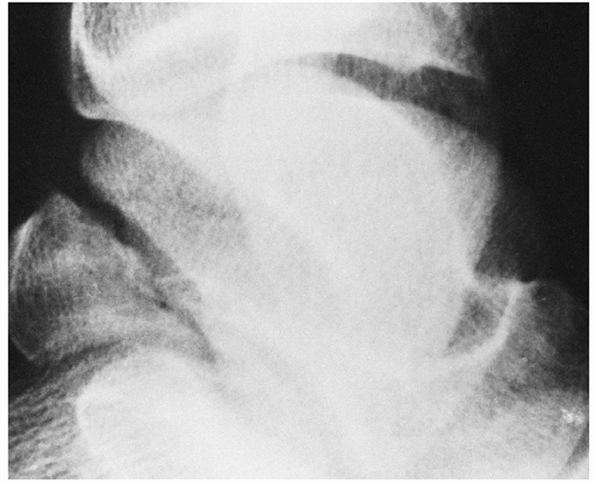

classification, type I refers to a fracture without associated joint

dislocation, that is, an undisplaced fracture of the talar neck (Fig. 58-3). As noted by Daniels, “There is no room for the term ‘a minimally displaced type I talar neck fracture.’”32

In equivocal cases, careful attention should be directed to the

subtalar joint alignment to confirm that there is in fact no degree of

subtle incongruity and to the clinical exam, as most slightly displaced

talar neck fractures are associated with deformity. Often the talar

head is rotated relative to the talar body, such that supination of the

midfoot and forefoot relative to the hindfoot can be noted.

FIGURE 58-3 Nondisplaced vertical fracture of the talar neck, Hawkins’ type I.